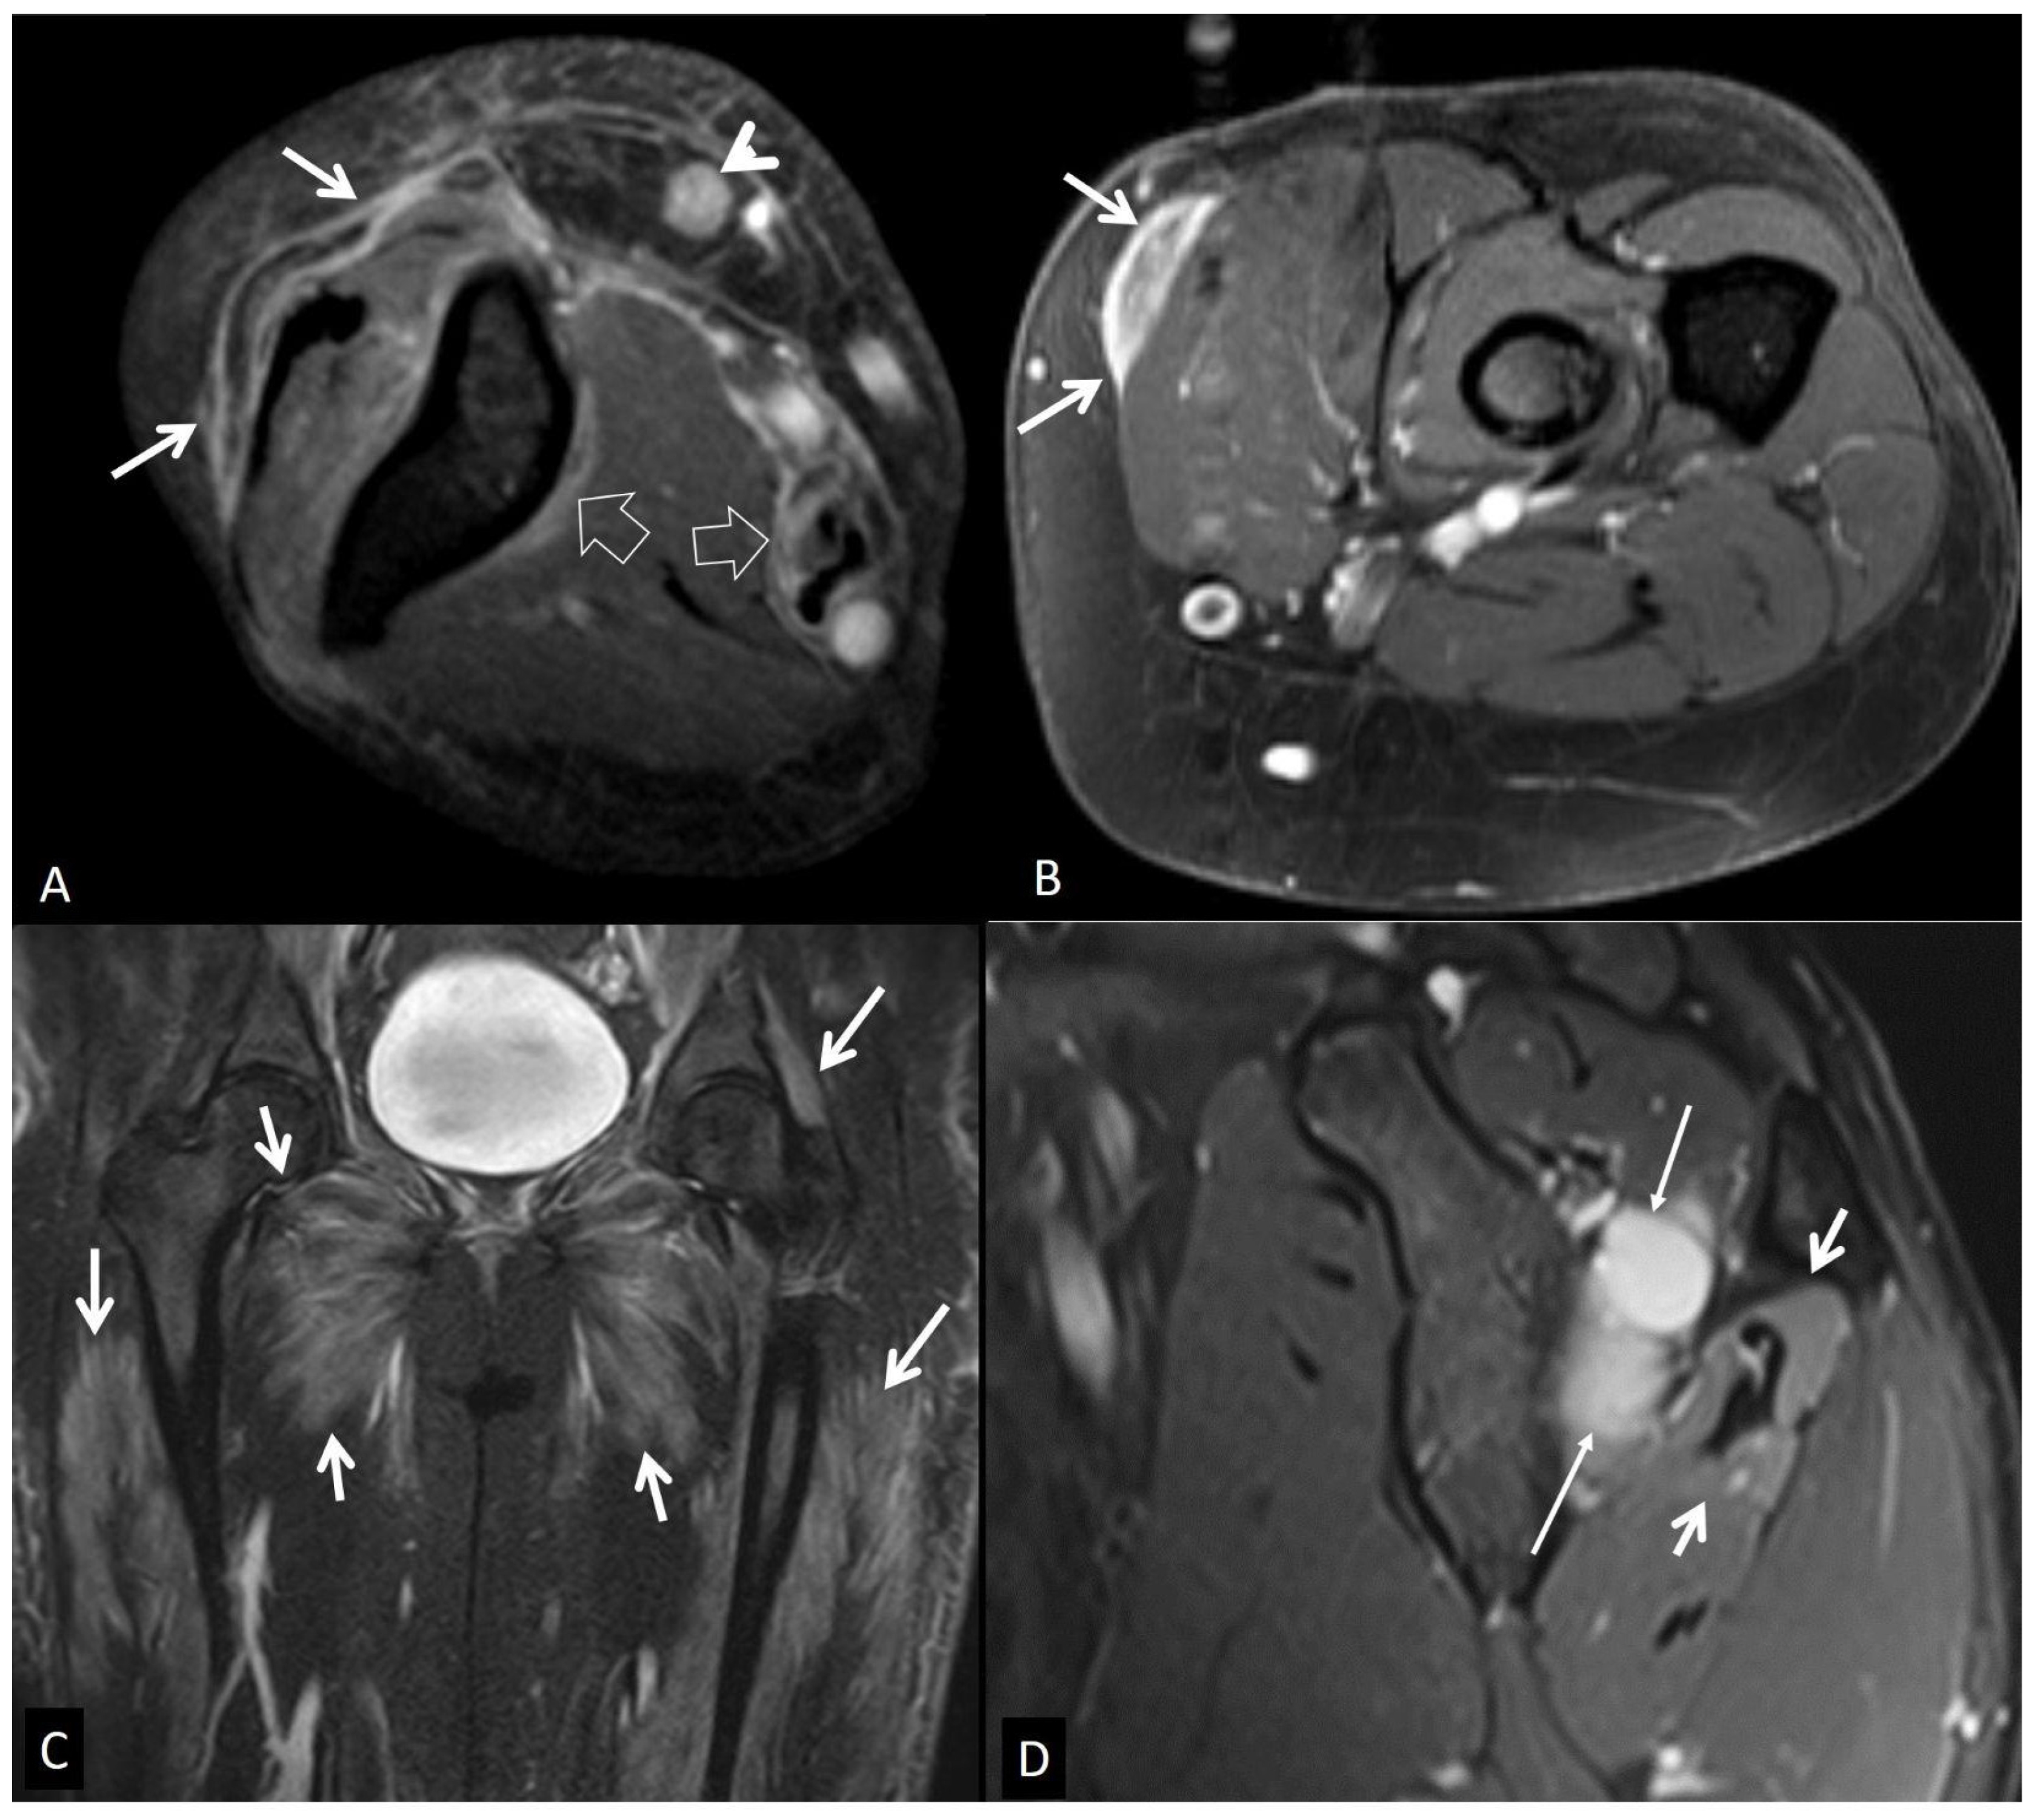

5. Muscles and Soft Tissues

5.5. Neoplasm and Post-Therapy Soft-Tissue Changes

5.5.1. Neoplasms

5.5.2. Post-Therapy Soft-Tissue Changes